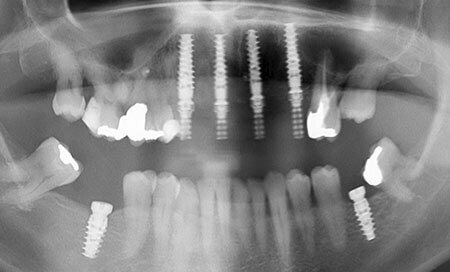

AVANT3 Le cliché panoramique montre la perte de substance sous les tenons et les couronnes, ce qui explique les descellements intempestifs

Le cliché panoramique montre les 4 implants répartis dans le prémaxillaire. Le bridge provisoire sera porté 6 mois jusqu’à la parfaite cicatrisation gingivale et osseuse. Un bridge d’usage transvissé démontable pourra alors être confectionné.